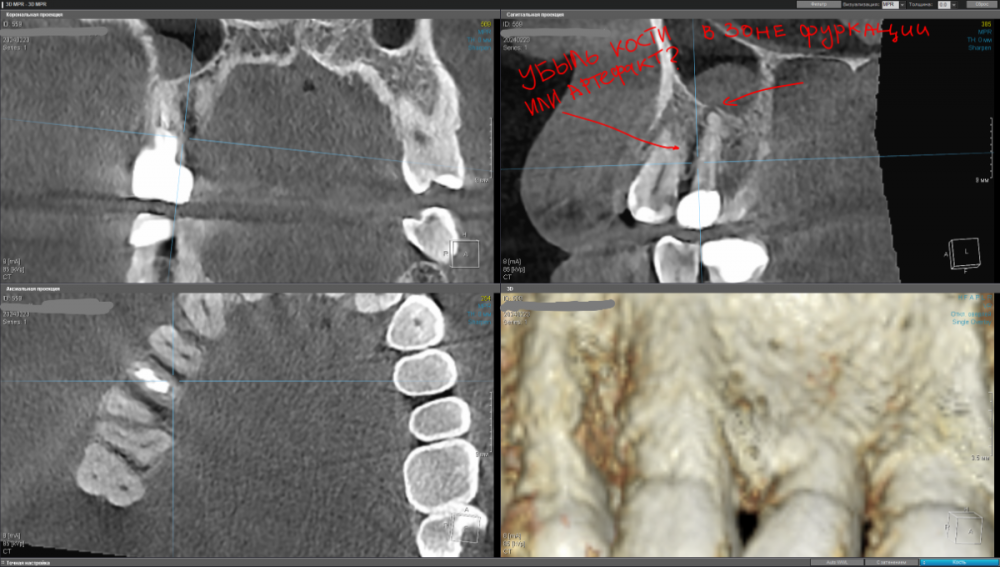

kamacho Опубликовано 24 февраля, 2024 Автор Поделиться Опубликовано 24 февраля, 2024 Попробую привлечь ваше внимание дополнительными снимками. Вопросы которые я себе задаю когда смотрю на КТ: 1) Между 14 и 15 зубом, это убыль фуркации или артефакт при съемке кт ? 2) В районе 37 ого зуба это артефакт или кариес ? Я пытаюсь санировать ротовую полость уже наверное лет пять, и никогда не удается решить проблему. Прошел множество клинник (наверное штук 5-6, включая 1 зарубежную). Но после попыток лечения, возникает одна и таже проблема, как только начинаю добавлять углеводы(не сладости) в рацион, какой-то очаг инфекции дает о себе знать. Буду очень признателен если поможете советом или догадкой. Ссылка на комментарий

Carioznik Опубликовано 25 февраля, 2024 Поделиться Опубликовано 25 февраля, 2024 15.02.2024 в 18:43, kamacho сказал: есть ли показания для лечения этого зубика? По идее есть, но нужно разбираться 15.02.2024 в 18:43, kamacho сказал: Могут ли не до конца пролеченные корни вызывать такую симптоматику ? Нет 17 часов назад, kamacho сказал: Между 14 и 15 зубом, это убыль фуркации Нет. Похоже, что на 14 есть кариес. Возможно это и причина кровоточивости и запаха. Но нужно смотреть настоящую КТ , а не скрины. 18 часов назад, kamacho сказал: районе 37 ого зуба это артефакт или кариес ? Больше на артефакт похоже, но это не точно: нужно смотреть настоящую КТ , а не скрины 1 Ссылка на комментарий